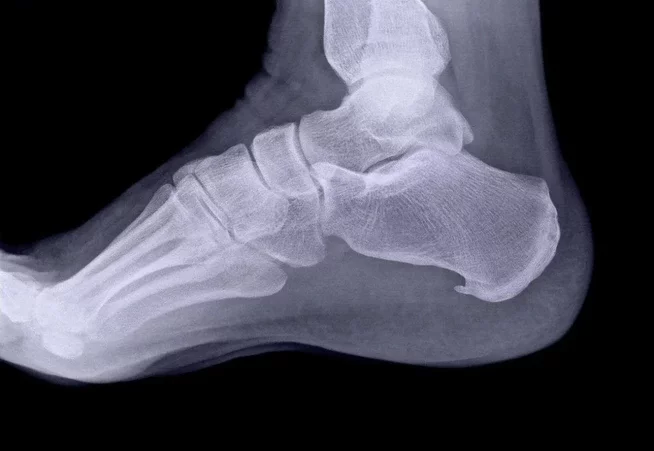

FOOT STRUCTURE

THE FOOT CONTAINS 26 BONES, WHICH ARE DIVIDED INTO 3 SECTIONS.

The forefoot contains the five toes (phalanges) and the five longer bones (metatarsals).

The midfoot is a pyramid-like collection of bones that form the arches of the feet. These include the three cuneiform bones, the cuboid bone, and the navicular bone.

The hindfoot forms the heel and ankle. The talus bone supports the leg bones (tibia and fibula), forming the ankle. The calcaneus (heel bone) is the largest bone in the foot.